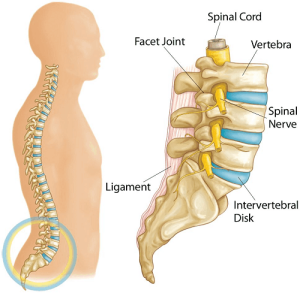

When we talk about a spinal disc, what we are actually talking about is a structure in your spine. The spine is made up of many bony segments called vertebrae and the structure in-between these segments are called your intervertebral discs (i.e. spinal disc).

It has a solid and strong exterior ligament component which provides stability and support, whilst there is a soft centre called the nucleus, which gives shock absorption of your body weight and for the various activities that you perform in a day. You could liken the disc to be a solid but gooey “lava-cake” sandwiched between crispy waffles.